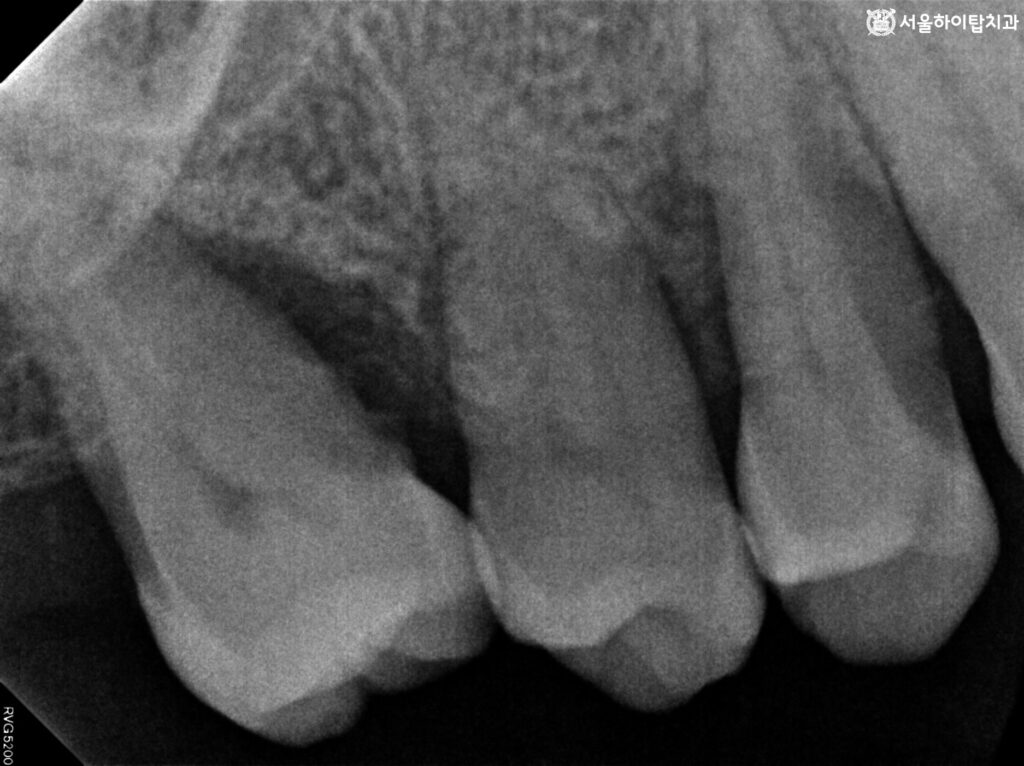

진단 – 치아 동요와 골 지지 상실

빨간색으로 표시한 선이 Bone level,

즉 현재 치조골의 높이를 나타냅니다.

이미 치근단 근처까지 뼈가 낮아진 것을 확인할 수 있는데,

이런 경우에는 당연히 치아가 충분히 지지받지 못하기 때문에

동요도(Mobility)가 증가할 수밖에 없습니다.

현재 골 소실 정도가 심하여 주안역 치과 에서는 Grade 3로 판단됩니다.

게다가 어금니는 보통 두 개 이상이 함께 존재해야

안정적인 지지를 제공하지만, 이미 하나가 상실된 상태입니다.

따라서 남아 있는 어금니는 골 흡수와 인접 치아 상실이 겹쳐

살짝 기울어진 모습으로 나타나는 것을 볼 수 있습니다.

구강 내 사진과 육안 관찰을 통해서도 치근이 드러난 모습을 확인할 수 있으며,

치아가 충분히 지지되지 않아 살짝 틀어진 위치까지 확인할 수 있습니다.